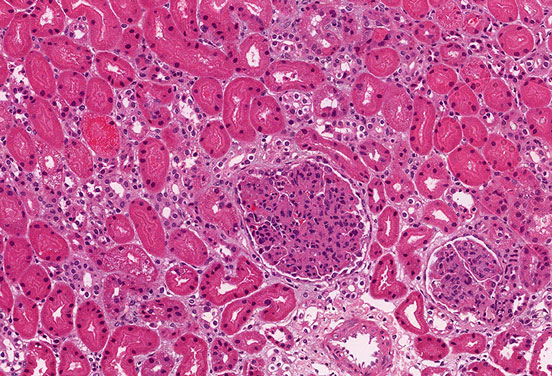

La biòpsia renal és un element de diagnòstic fonamental en el camp de la Nefrologia. Les malalties del ronyó tenen una traducció en l'estat general de la persona i també es revelen en les analítiques de sang i orina practicades. De la mateixa manera les proves d'imatge (ecografia renal, TAC, ressonància nuclear magnètica), donen informació sobre el diagnòstic de la malaltia renal, però la prova bàsica i imprescindible per al diagnòstic de la malaltia renal és la biòpsia renal.

La mostra obtinguda es processa pel Servei d'Anatomia Patològica amb l'ús de diferents tècniques per a l'observació sota microscòpia òptica, microscòpia de fluorescència i microscòpia electrònica. Així es poden observar els diferents compartiments del ronyó: els glomèruls, els túbuls, i els vasos sanguinis. També es poden fer tincions especials per a revelar infeccions i toxicitat produïda per diferents fàrmacs.